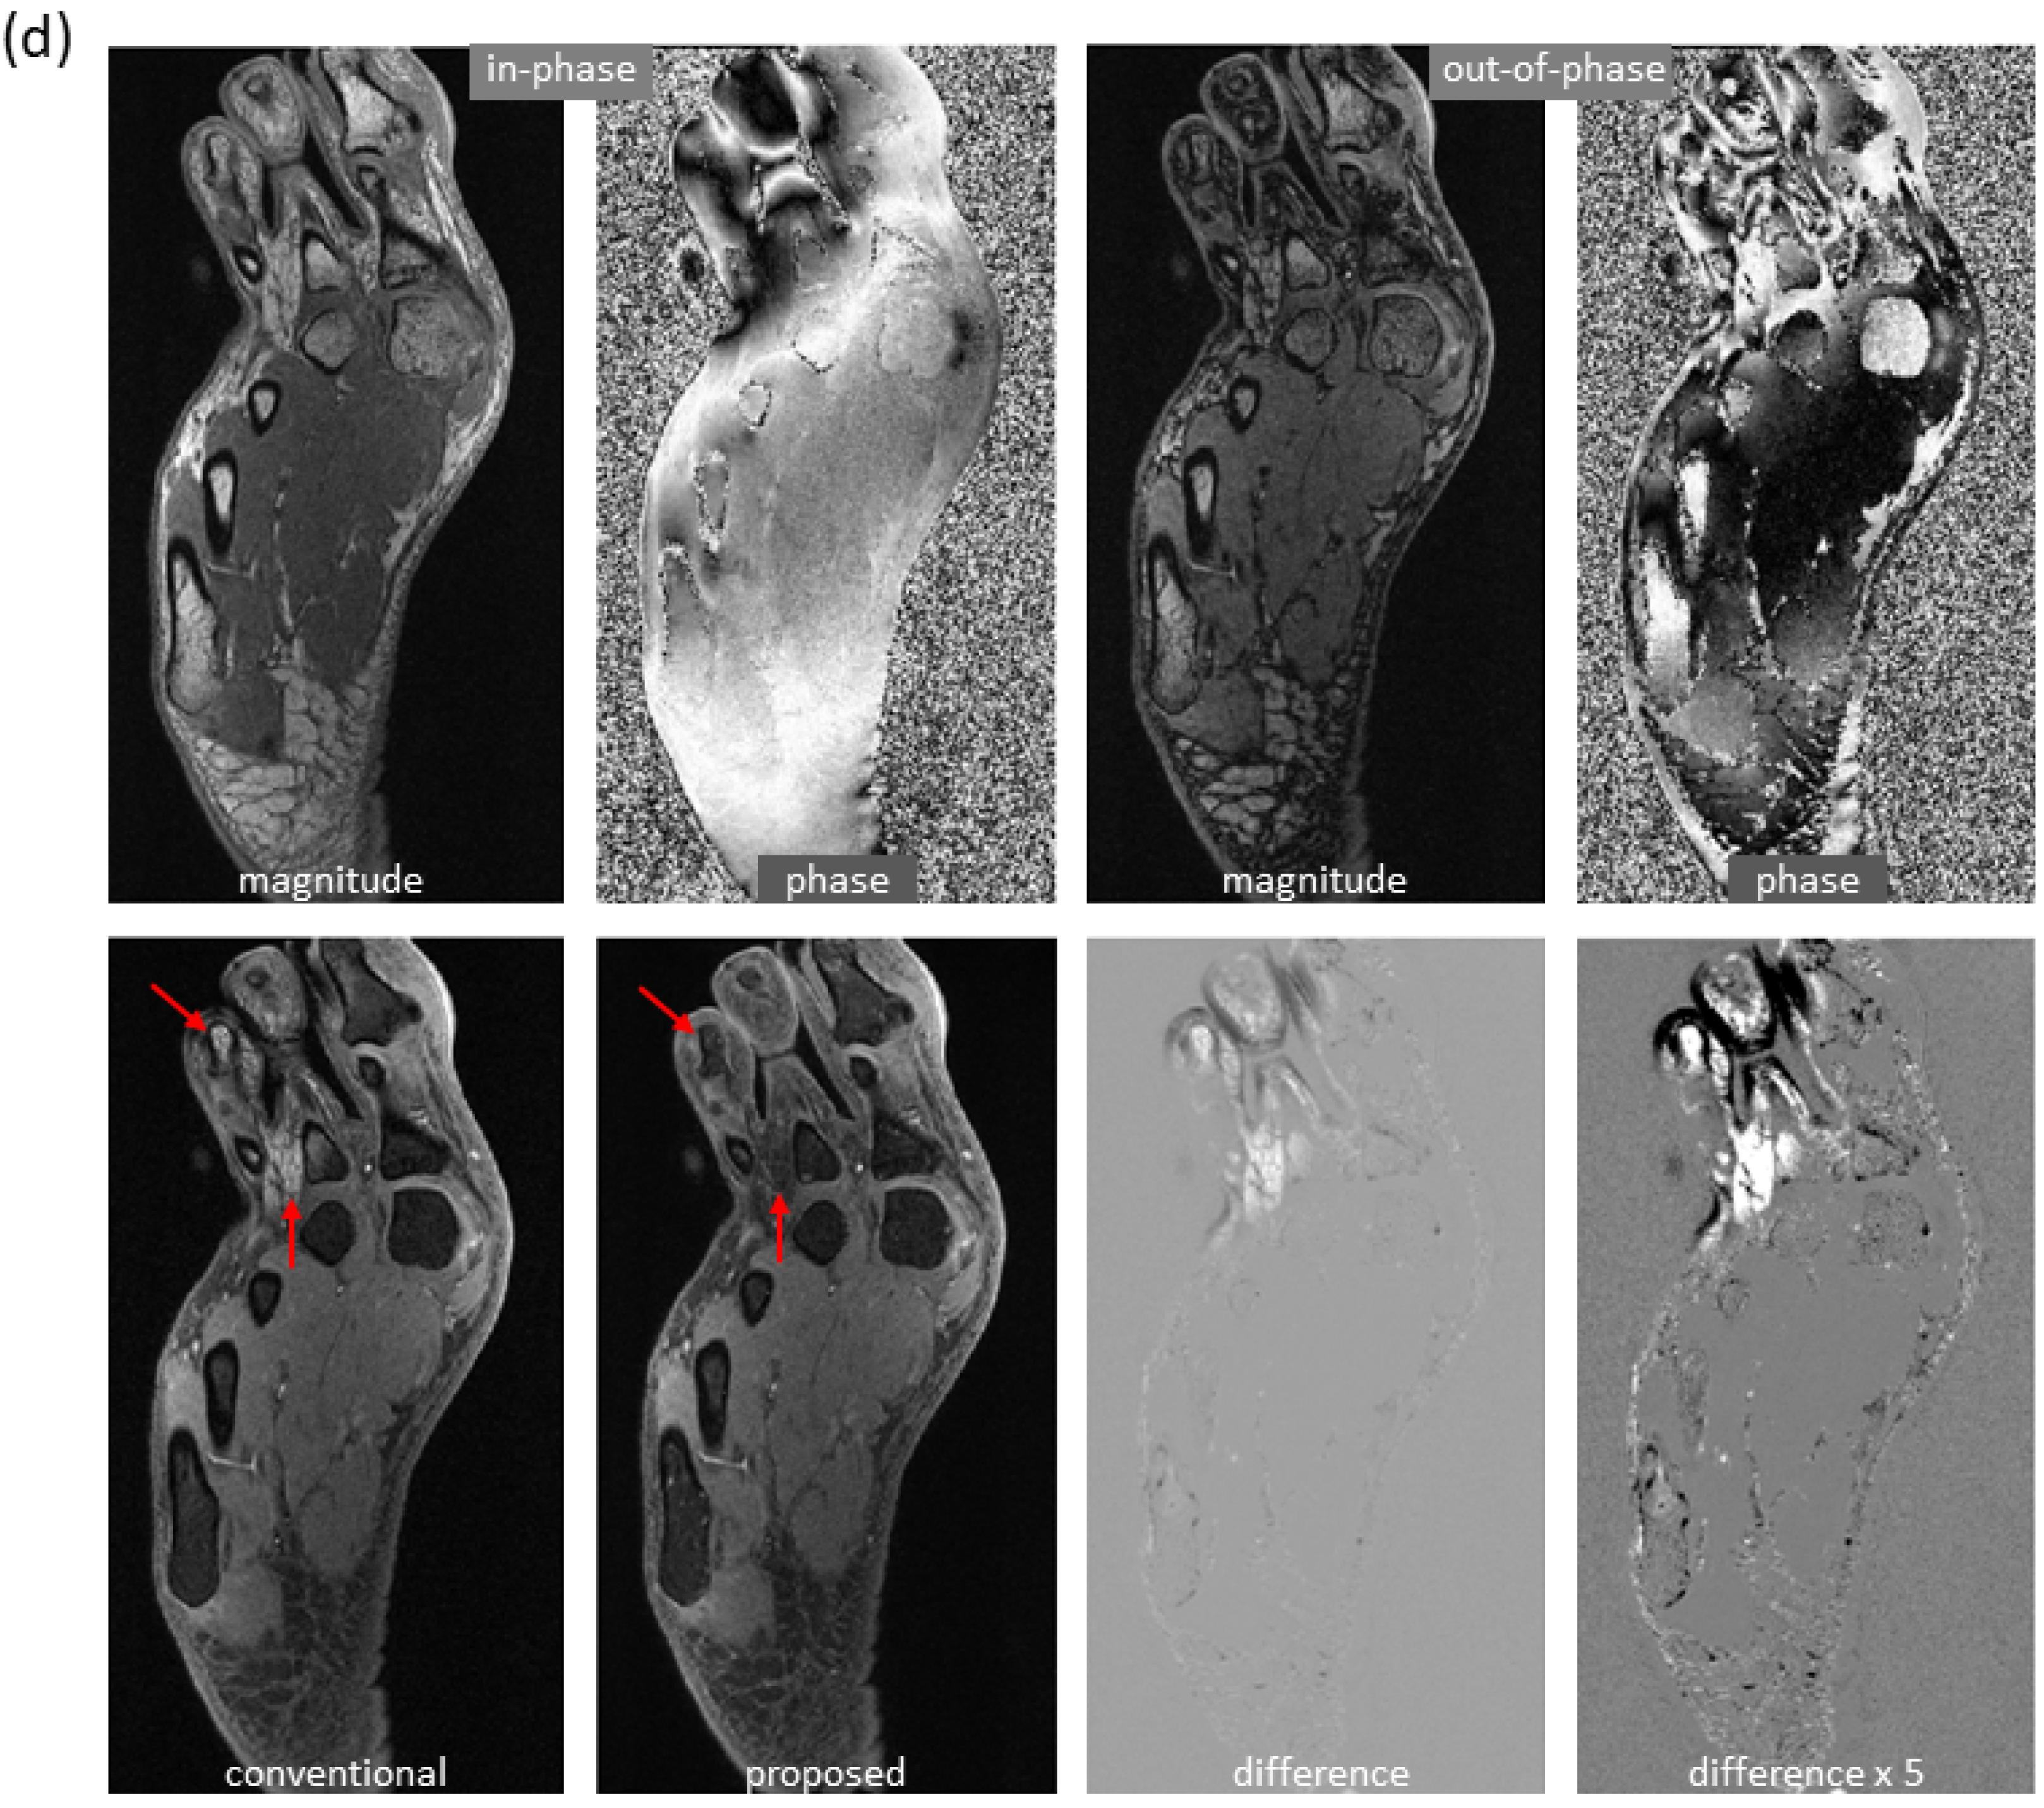

More examples with severe local water/fat swaps as well as global water/fat swaps are shown in Figure 5. In an ankle examination (Figure 5a), as the slices moved farther from isocenter, progressively severe water/fat swaps occurred in the peripheral region of reference images; the water/fat swaps were corrected in the predicted images. In a foot examination (Figure 5b), severe water/fat swaps appeared in the reference images (the dashed arrow pointed to an accessory ossicle with edema, and a local swap appeared in its marrow); the predicted images only had a few smaller swaps. In a knee study (Figure 5c), global water/fat swaps occurred, which in fact was not uncommon in conventional water–fat separation. Using the proposed method, global water/fat swaps were eliminated, and a slightly improved spatial resolution was observed, which can be attributed to the use of convolution for upsampling (expected to outperform conventional upsampling processing).

Figure 5.

Marked correction of severe water/fat swaps. (a) In an examination of the ankle, progressively severe water/fat swaps occurred in the reference images as they moved farther from isocenter (every ninth slice is shown). In the predicted images, the water/fat swaps were completely corrected. (b) In an examination of the foot, severe water/fat swaps appeared in the peripheral region of the reference images, where the dashed arrow showed an accessory ossicle with marrow edema that also had a local swap in its marrow. The water/fat swaps were substantially compensated in the predicted images, which only had smaller regions of swaps (solid arrows). (c) Global water/fat swaps, which occurred in the reference image, were corrected using the proposed deep learning method. An improved spatial resolution was observed in the predicted image.